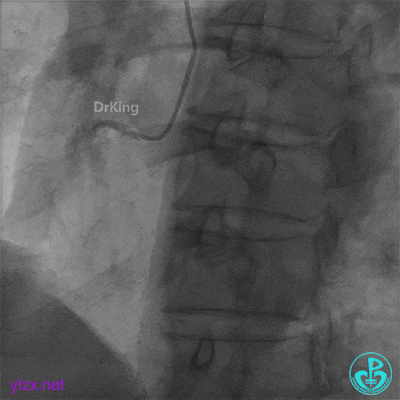

心脏叩击后恢复窦性心律,阿托品1mg静推,去甲肾上腺素静脉滴注,冠脉内推注尿激酶原20mg。

快速串联植入3.5×29mm、3.5×23mm支架。

并反复经刺破球囊冠脉内静推硝普钠5次(100μg/次),右冠脉血流恢复TIMI 3级,右冠脉近端可见夹层。

支架近端植入3.5×13mm支架覆盖夹层。

最后结果示右冠脉近端支架外仍然可见夹层。